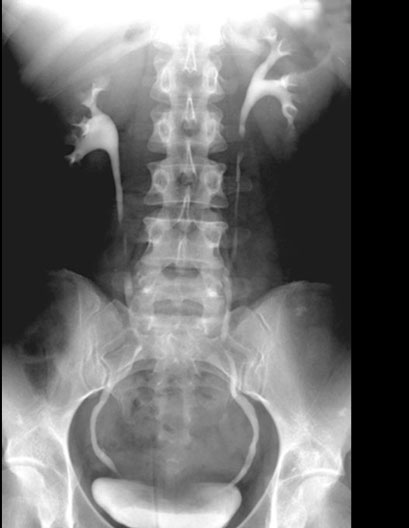

Kidney Intravenous Pyelogram

Roll mouse over image to display labels.

1. Minor calyx

2. Major calyx

3. Ureter

4. Bladder